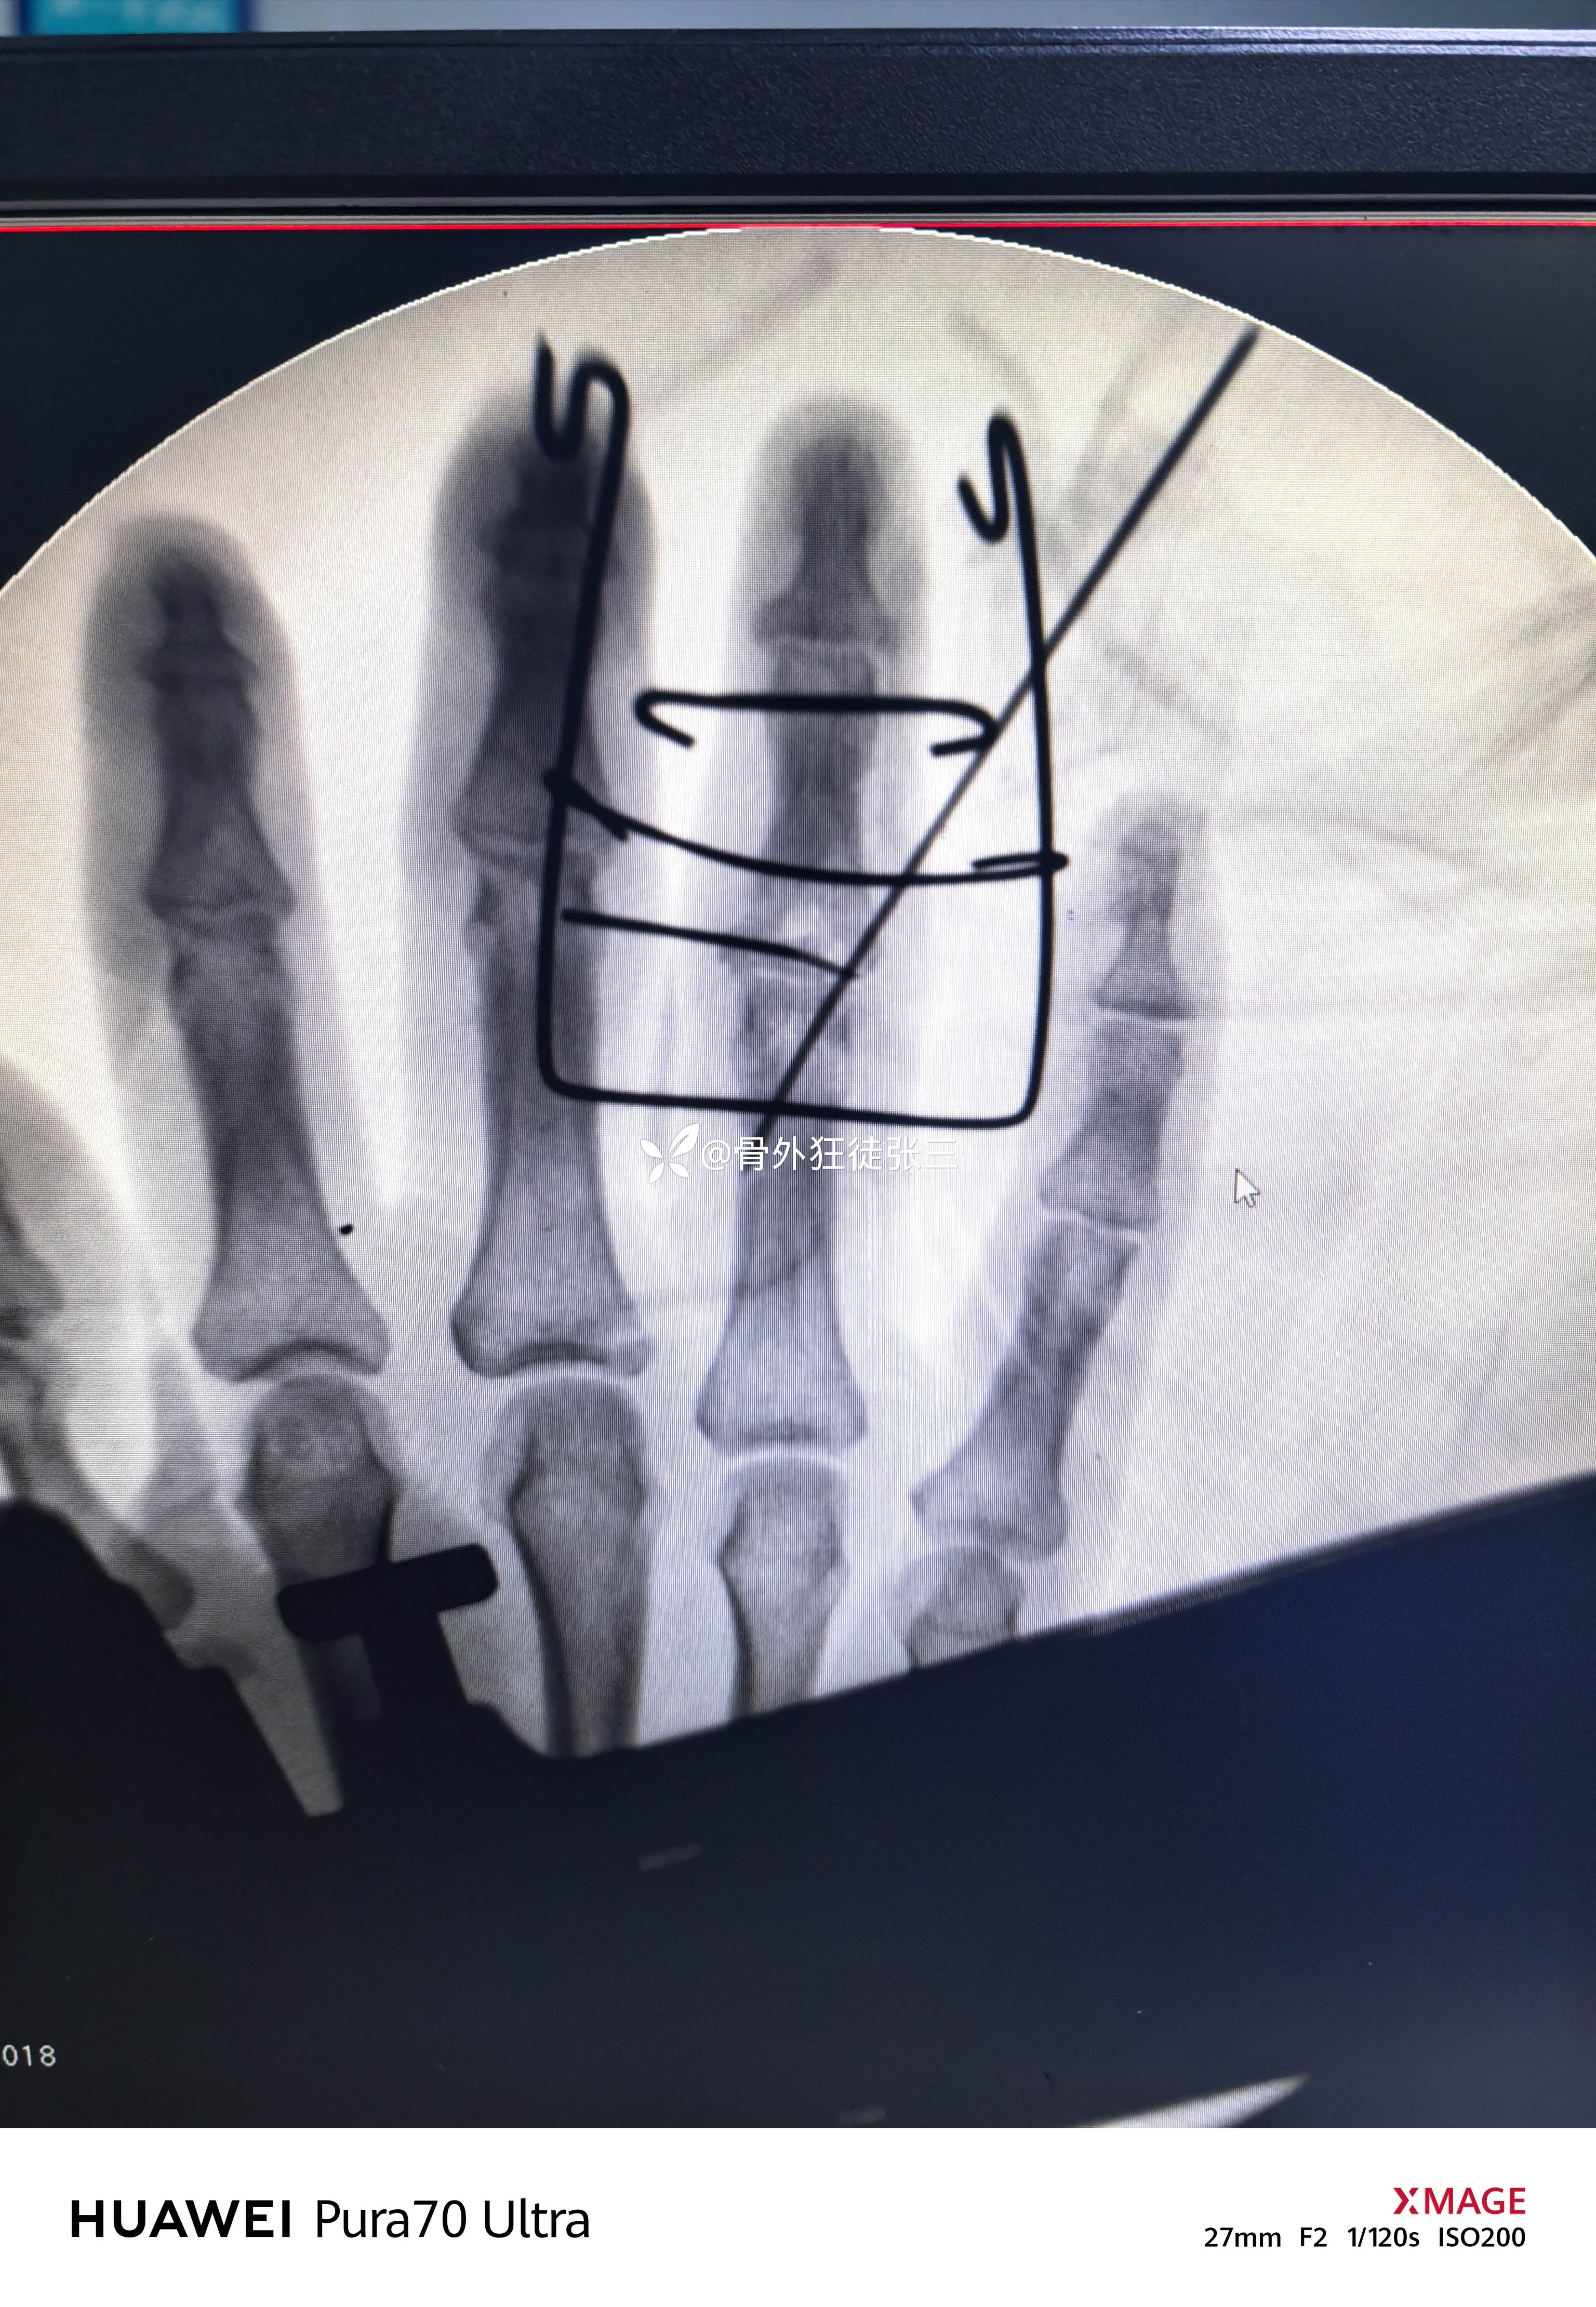

透视发现骨块复位

关节复位

五,术后处理

1,弹力带持续牵引

2,关节部位的克氏针固定3周

3,3周后开始动态牵引下功能锻炼

4,4+6周复查X线,愈合后拔针。